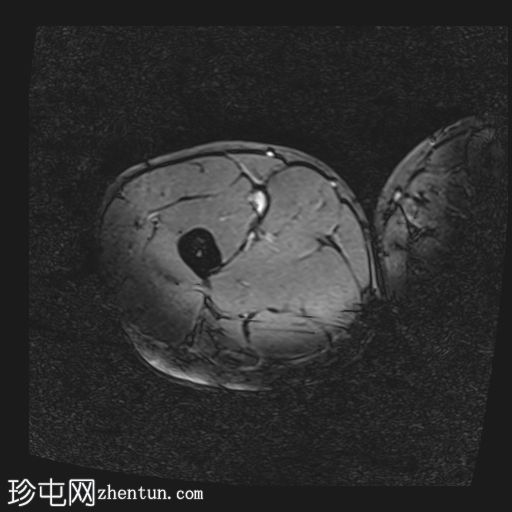

轴位

T2-fl2d-hemo

内收长肌和内收短肌中远侧外侧可见羽状改变和肌内水肿,主要累及内收大肌,长15厘米,宽4厘米。未见明显血肿或完全性肌纤维撕裂。

后腱膜、邻近神经血管交界处及邻近肌间隙可见积液,少量积液向外侧扩散,沿肌间隙到达大腿中远侧。

影像学特征符合英国田径肌肉损伤分级(BAMIC/BAC)2B级损伤,主要累及大收肌。未见明显的血肿或肌纤维完全撕裂。